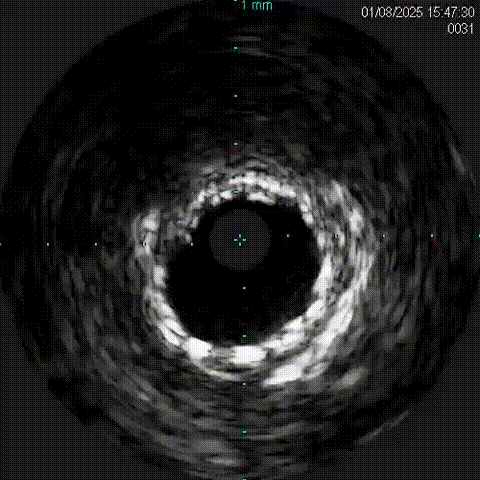

右冠血管内超声影像(IVUS)

对侧造影证实GW3位于远端真腔,跟进微导管,撤出GW3送入GW1,先后送入balloon 1(1.5x1.5mmEmerge)、Ballon 2(2.0x15mmGusta)、Ballon3 (2.0x15mm 心迅)、Ballon 4(2.5x15mm cutting)、Ballon5(2.5x15mm NC Sprinter)、Ballon 6(3.0x15mm NC Sprinter)至RCA病变处预处理后,送入IVUS查看病变性质、程度及血管直径。